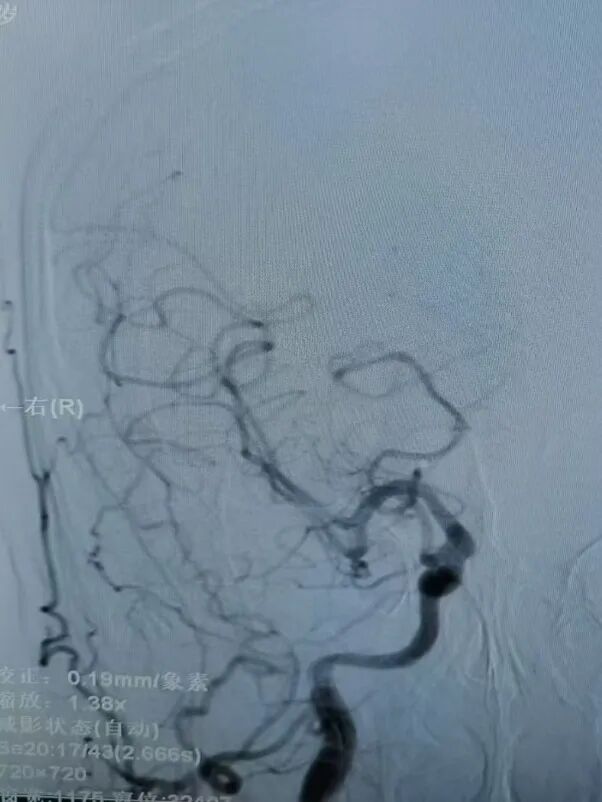

支架植入后造影,右侧颈动脉及大脑中动脉血流通畅,支架位置良好。

动脉长鞘怎么置入有励可说|Locaste 088励楷长鞘在右侧颈内动脉闭塞并夹层术中的应用_https://www.jmylbn.com_新闻资讯_第15张

动脉长鞘怎么置入有励可说|Locaste 088励楷长鞘在右侧颈内动脉闭塞并夹层术中的应用_https://www.jmylbn.com_新闻资讯_第16张

动脉长鞘怎么置入有励可说|Locaste 088励楷长鞘在右侧颈内动脉闭塞并夹层术中的应用_https://www.jmylbn.com_新闻资讯_第17张